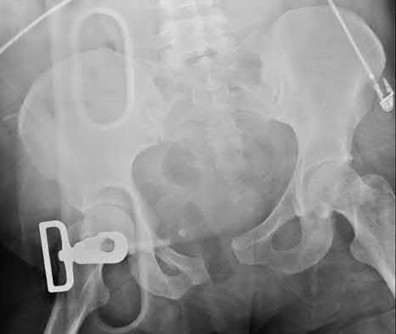

OrthoCash 2020 -

During head-on motor vehicle collisions occurring at highway speeds, airbag-protected individuals have a decreased rate (as compared to non-airbag protected individuals) of all of the following EXCEPT:

Corrent answer: 4

The referenced study by Loo et al. studied the interaction between airbags/seatbelts and mechanism of the crash (ie. front vs. side impact) and the injury patterns in these patients. They found that in frontal crashes, airbags reduced Glasgow Coma Scale severity in brain injury, facial fracture, shock, thoracoabdominal injuries and the need for extrication. Frontal airbags also had a protective effect on lower extremity fractures, but had no significant protective effect on pelvic fractures.